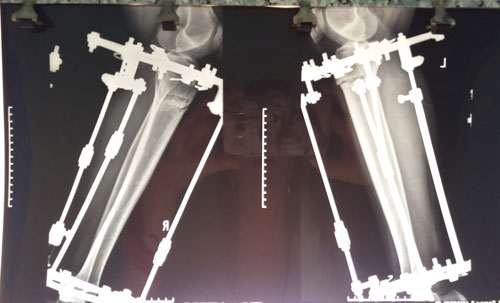

Исходник - 36 лет. Актау.

Дата операции - 19.06.2018г.

Дата снятия аппаратов 19.09.2018г.

Срок лечения 90 дней.